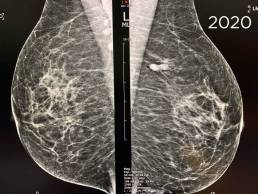

Cas de la semaine (semaine 35, 2021)

Mammographie de dépistage. Patiente de 73 ans

L’examen est comparé à l’examen de 2018, il existe 2 opacités accolées du prolongement axillaire gauche présente sur l’examen de 2018 évoquant des ganglions intramammaires.

Pourtant, Mammoscreen™ pointe ces lésions et met un drapeau rouge.

La mammographie est tout de même considérée bénigne et envoyée en seconde lecture.

Le second lecteur demande un complément échographique et un cliché localisé devant l’augmentation des lésions entre 2018 et 2020.